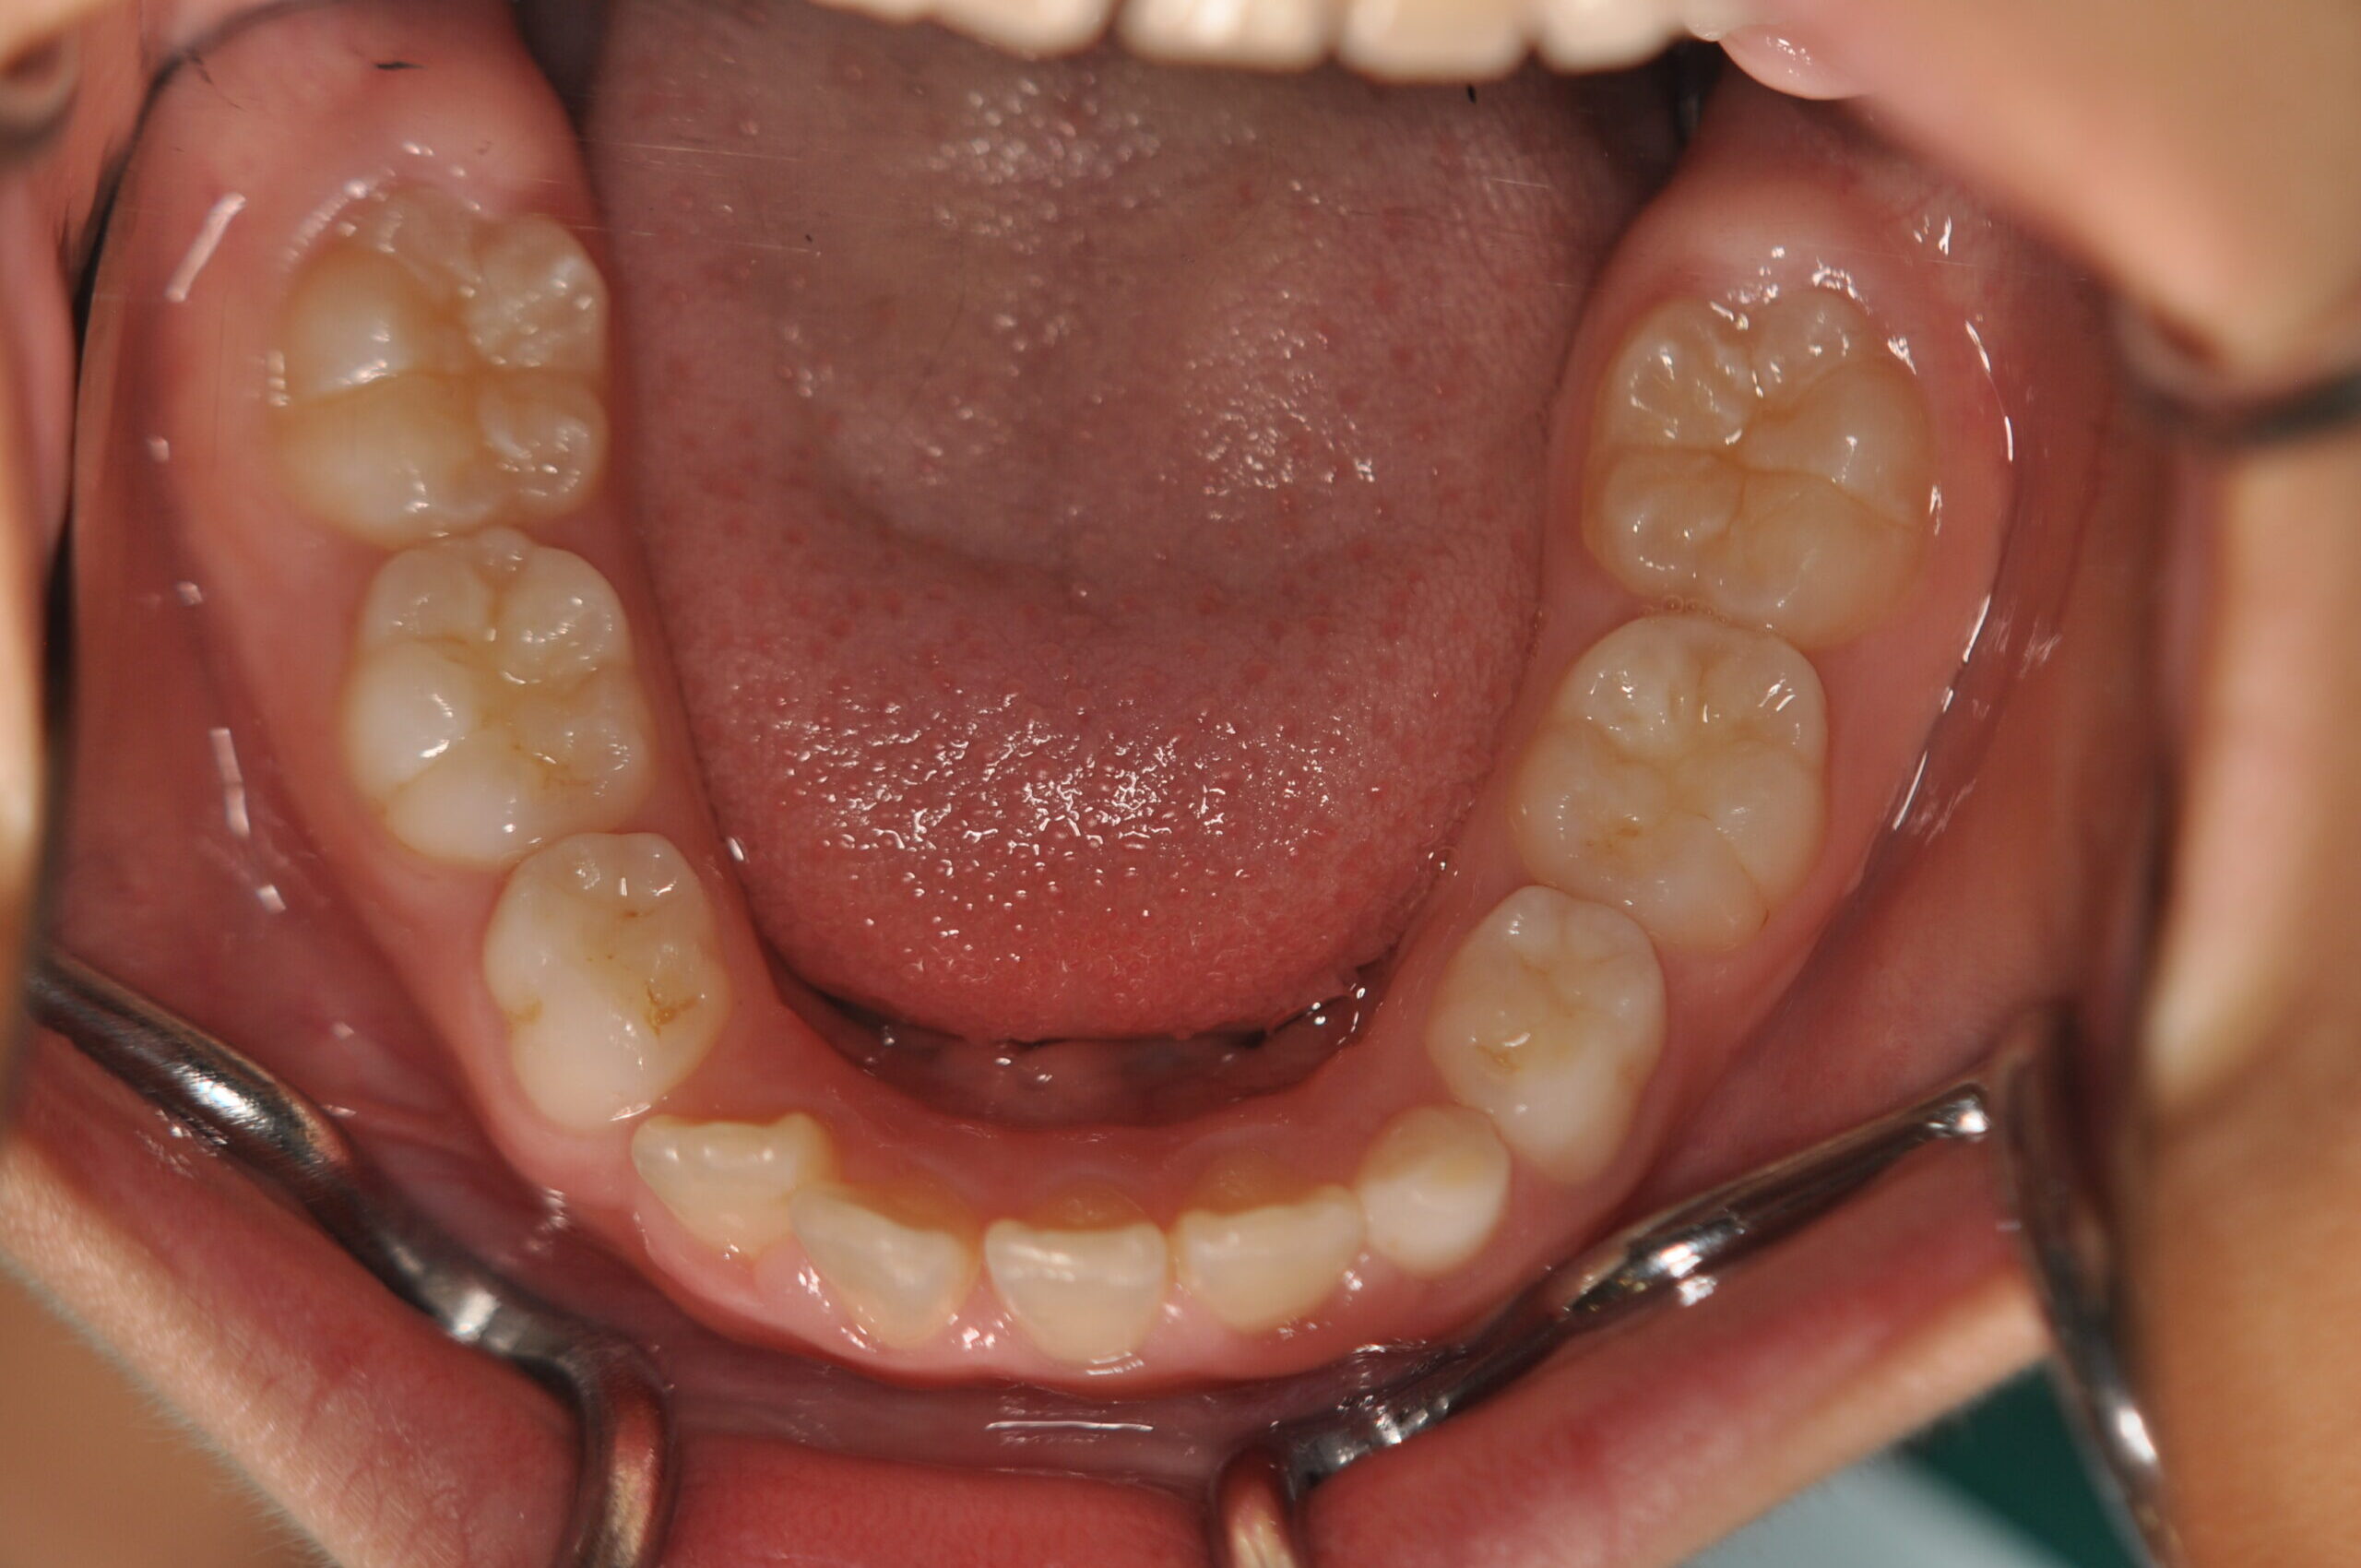

動的治療終了時

症例 症例 症例 症例

永久歯列に交換後、非抜歯の上、セルフライゲーションブラケット装置(デーモンシステム)で歯の配列と咬合関係の改善を行いました。

治療期間は、5年10ヶ月でした。